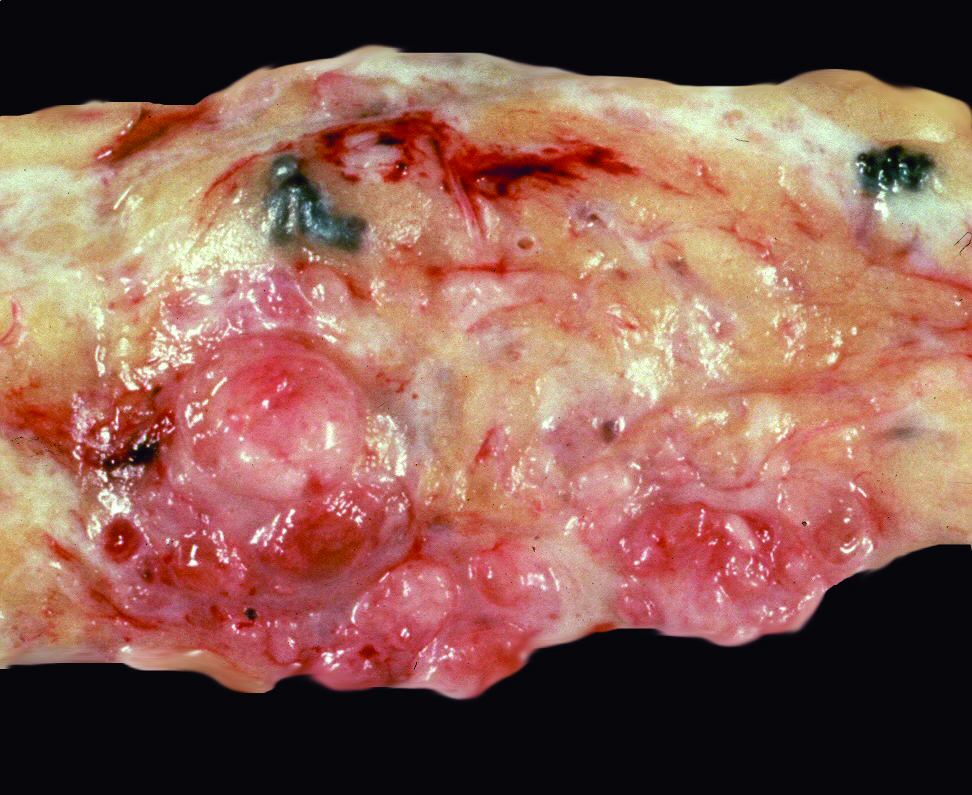

Gross description

- Rounded, shelled out borders

- Infiltrative in malignant and less commonly borderline phyllodes tumor

- Whorled, bosselated cut surface in a leaf-like pattern

- Skin ulceration, hemorrhage and cystic changes in large lesions (Int J Surg Case Rep 2020;67:114)

- Ulceration and hemorrhage do not indicate malignant behavior per se

- Infarcted or very large benign phyllodes tumor can also show necrosis

Gross images